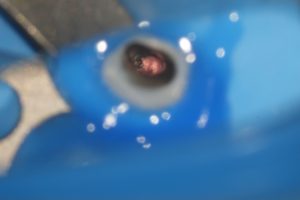

【外科的根管治療 頬側の骨がすでに吸収していて遠心側の歯根が露出している】